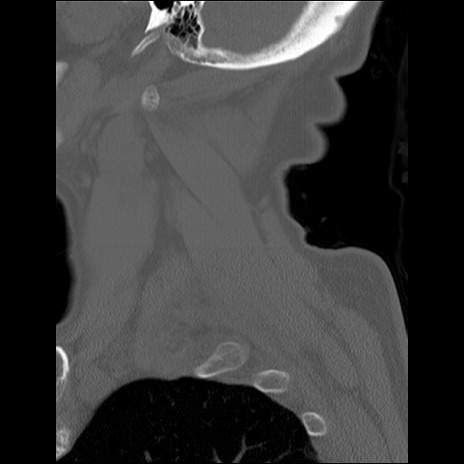

症例48 頚椎CT(矢状断像)

頚椎CT